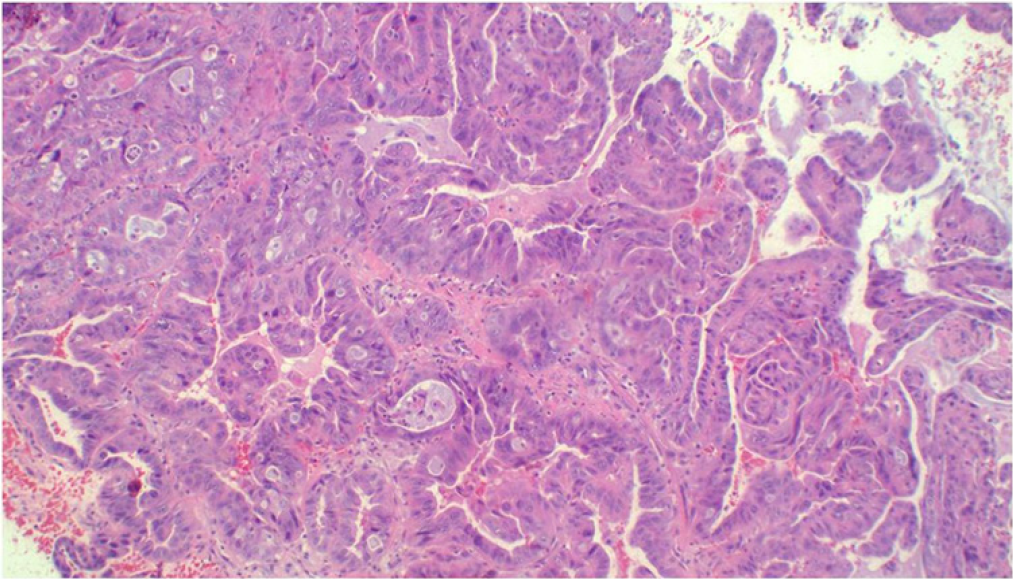

Introduction: Gallbladder carcinoma is a malignant epithelial neoplasm of the gallbladder. The tumor is clinically aggressive, with an overall 5-year survival rate of < 10%. Cholelithiasis is a known and established risk factor. Up to 50% of gallbladder tumors are detected incidentally in routine cholecystectomy specimens due to the absence of gross abnormalities. Gallbladder carcinoma has several unusual presentations, one of which is an incidental pseudocyst with cholelithiasis and perforation. This unusual occurrence makes the index case unique.

Conclusions: Systematic sampling of cystectomy specimens is therefore crucial to detecting incidental gallbladder adenocarcinomas.